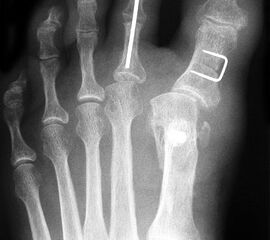

4) Augmentation der lateralen Kapsel durch ein ThightRope™ System

Eine isolierte Instabilität der lateralen Kapsel lässt sich auch mit einem ThightRope™ System (Fa. Arthrex, Naples, Florida) behandeln 17. Über ein Bohrloch im Kapselbereich des Metatarsale I und ein weiteres Bohrloch in der Grundphalanx wird der Faden des ThightRope™ Systems zur Verstärkung der lateralen Gelenkkapsel eingezogen (Abbildung 12 und 13). Es ist darauf zu achten, dass der Faden in der Gelenkachse verläuft, da ansonsten die Grundphalanx nach dorsal oder plantar gezogen wird mit entsprechender Bewegungseinschränkung.